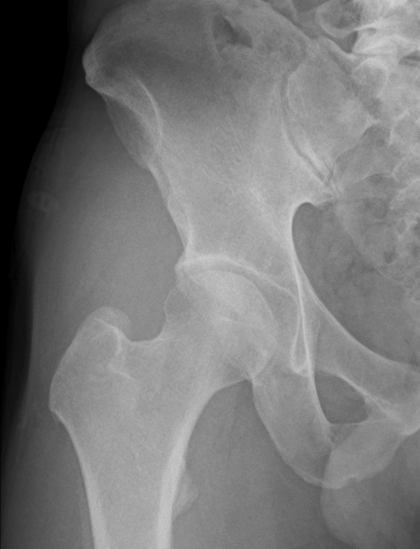

画像検査

X線(レントゲン)検査が基本となり、関節軟骨の厚みの減少(関節の隙間の狭小化)、骨棘(こつきょく:骨のトゲ)、骨嚢胞(こつのうほう:骨の中にできる空洞)の形成などを確認します 。必要に応じて、MRI検査で軟骨や周囲の軟部組織の状態をより詳細に評価します 。血液検査は、他の炎症性疾患との鑑別のために行われることがあります。

病期分類

X線所見に基づき、病気の進行度を前期、初期、進行期、末期のように分類し、それぞれの段階に応じた治療方針を決定します。